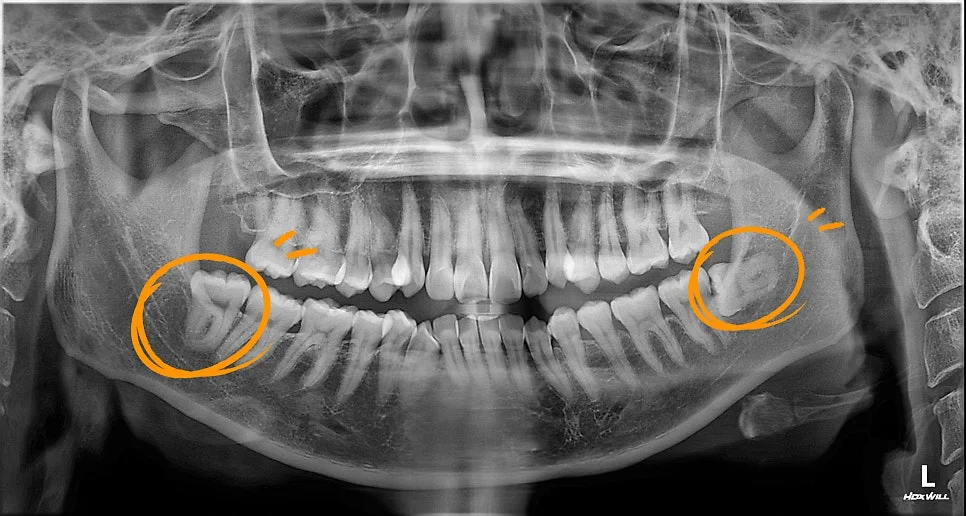

파노라마 사진 — 양쪽 아래 사랑니가 모두 매복돼 있는 상태

내원해서 찍은 파노라마 사진을 보면, 양쪽 아래 사랑니가 둘 다 매복돼 있죠.

특히 왼쪽 사랑니는 뼈 속 깊이 옆으로 누워 있으면서 바로 앞에 있는 두 번째 큰 어금니(제2대구치)를 꽉 눌러주고 있었어요.

이렇게 되면 앞어금니가 충치가 생기거나 뼈가 녹는 문제가 생길 수 있어서 발치가 꼭 필요했습니다. 게다가 신경관이랑도 가까워서 더욱 신경 써야 했죠.

이러한 경우, 매우 어려운 사랑니 발치로 볼 수 있습니다.